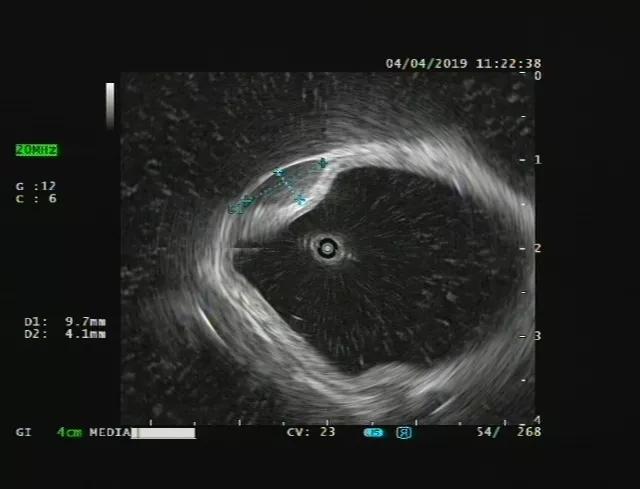

比如我们发现了十二指肠一个粘膜下隆起(下图),但是无法判断他的性质。

通过超声内镜,我们可以看出它在哪一层,是什么结构、什么性质。见下图: